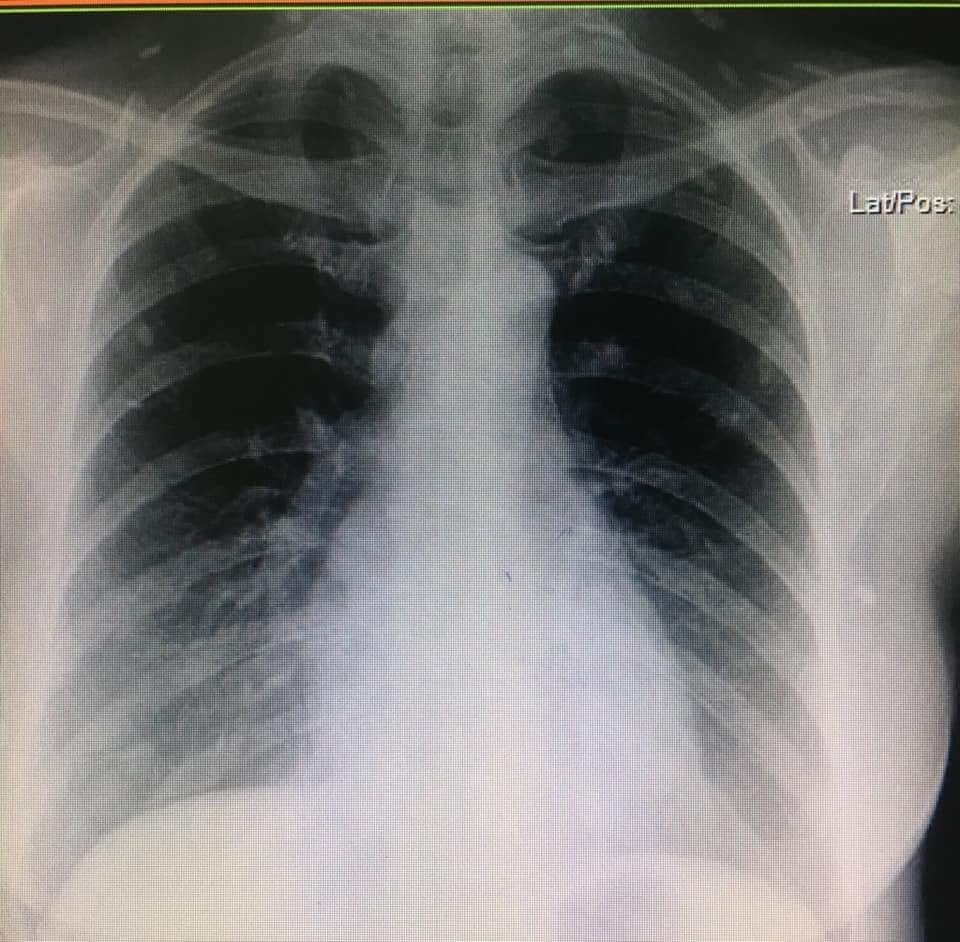

cc : หายใจลำบาก คอไม่โล่ง มีเสมหะในคอ O2sat 98% lung – clear pharynx not inject

me : คิดในใจไป CXR หน่อยก็ได้

แล้ว film ก็มา เลยไป film femur ต่อ

#cysticercosisจากหนังสือมาสู่ของจริง

#พยาธิตืดหมู